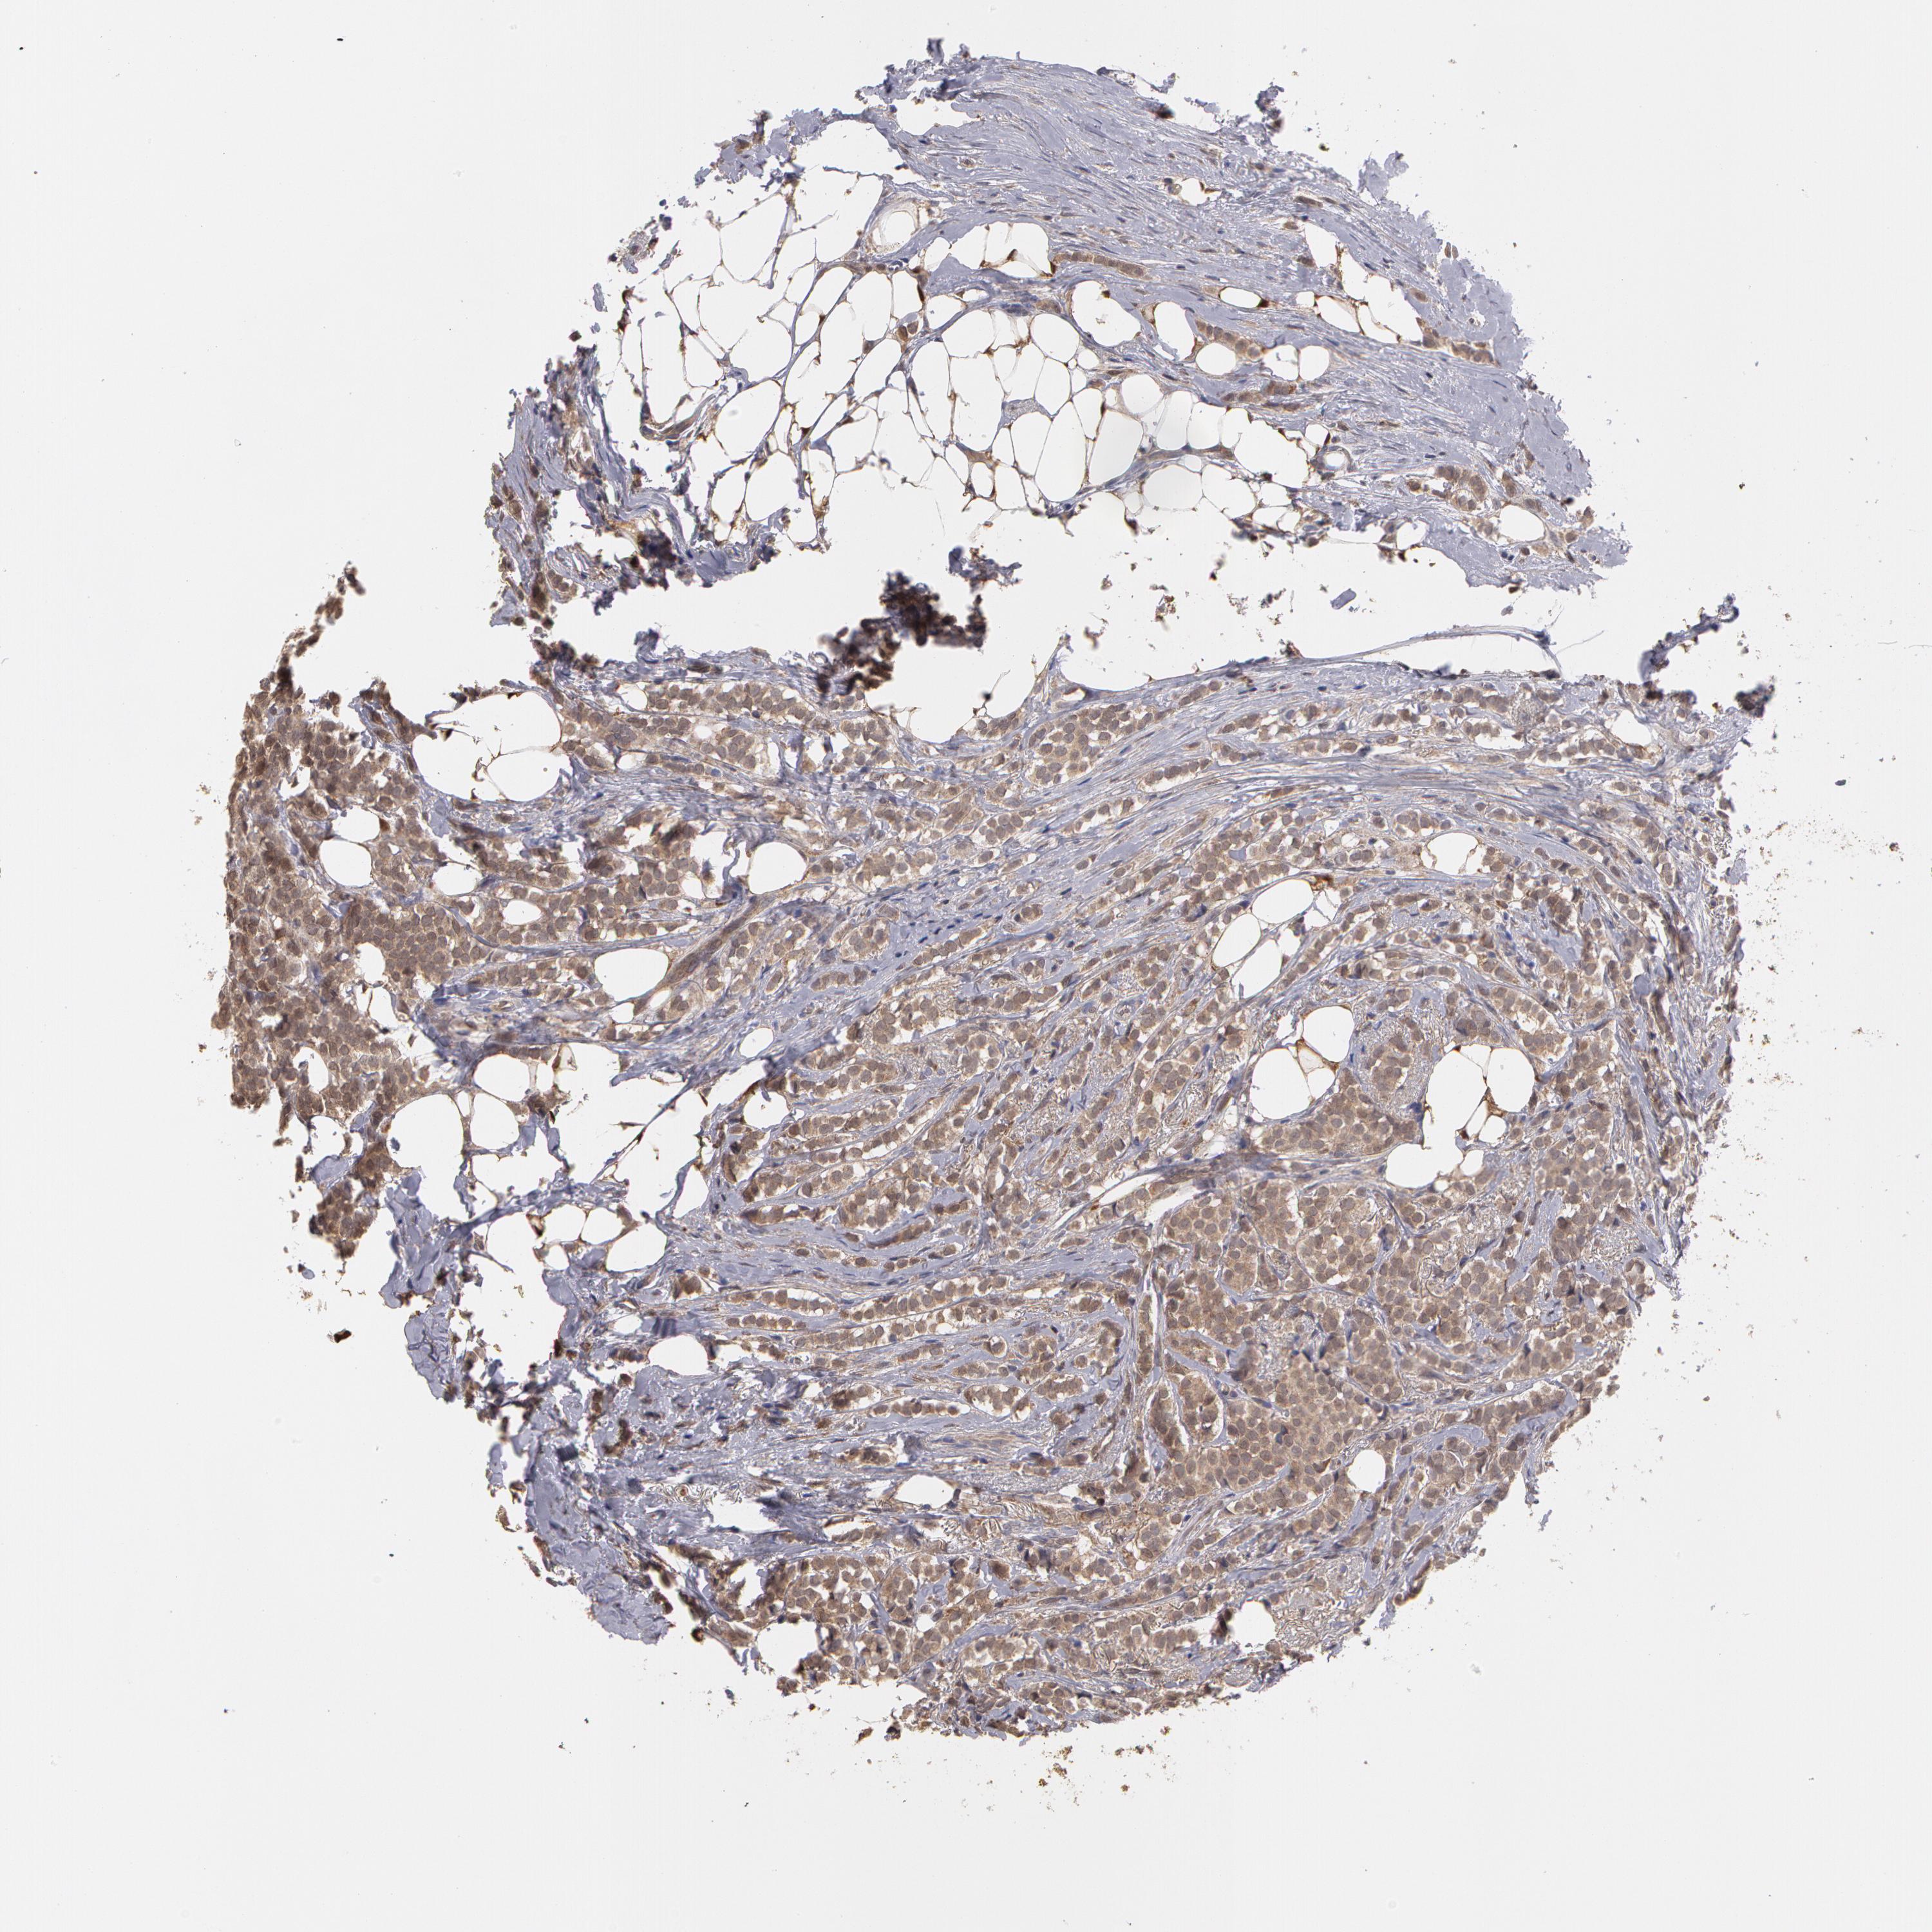

BRCA TCGA BRCA VALIDATION PROTEIN EXPRESSION